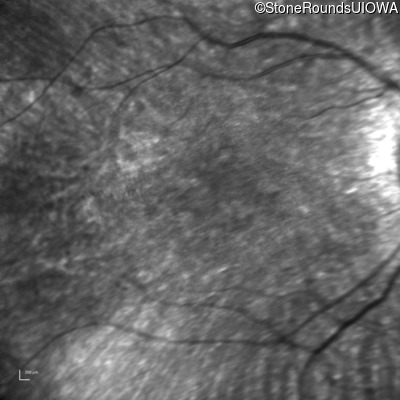

Age at visit: 10 years

OD OS